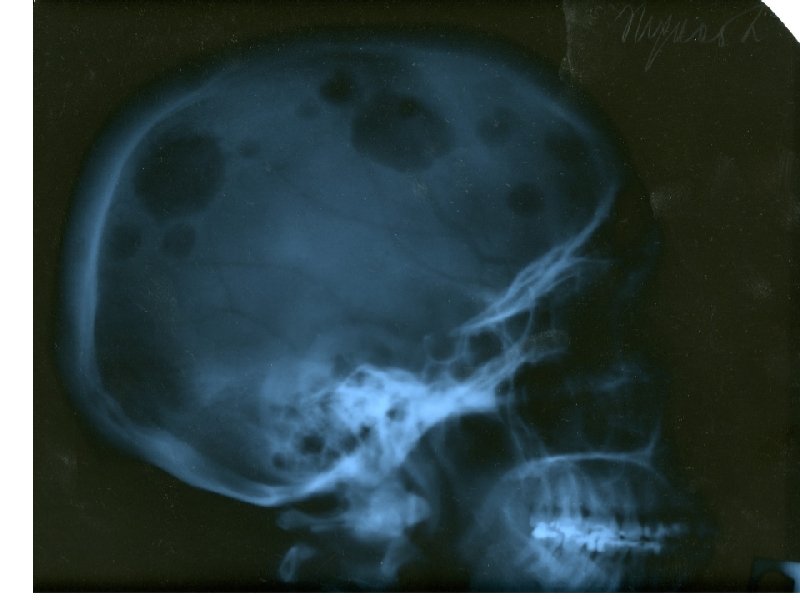

Клинические проявления ММ • Множественные остеолитические очаги Поражение костей повреждения плоских костей и эпифизов трубчатых костей • Диффузный остеопороз (остеопения) • Костные переломы • Уменьшение роста (вертебральный коллапс) Эффекты, ассоциированные с остеодеструкцией Внекостные плазмацитомы • Болевой синдром у 20 -40% Гиперкальциемия ( утомляемость, жажда, тошнота, запоры, повреждение почек, полиурия, сонливость, судороги, кома) • Гиперкальцийурия • Вовлечение мягких тканей преимущественно в области головы/шеи, очаги в печени, почках,

• Электрофорез –иммунофиксация (сыворотки или • • концентрированной мочи) Количественная оценка уровня иммуноглобулинов сыворотки крови Рентгенологическое исследование костей, КТ, МРТ, ПЭКТ, сцинтиграфия костей скелета, денситометрия Аспирационная биопсия костного мозга, трепанобиопсия СРБ, в 2 -микроглобулин, ЛДГ, ИЛ-6 Определение пролиферативного индекса и количества Ki-67 -положительных плазматических клеток Цитогенетическое исследование Иммунофенотипирование?

А- рентгенограмма, В- мультидетекторная КТ (МДКТ), Смагнитнорезонансная томография (МРТ)

А-ренгенограмма, В-МДКТ